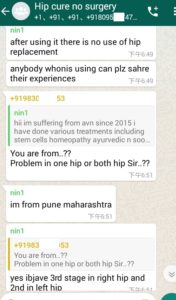

Following are some oversea patients recent feedback

Newly progresses(more will be uploaded soon)!

1. The Gentleman in Kenya started his treatment at his home April 27, now he said: (will update his more progresses soon)

3. The gentleman in India just started May, 2019. Actually he started on April 28, 2019 but he used it in wrong way and got less effects, ONLY on May 8, 2019 during our follow-up, we found his wrong-doing, and then corrected him. ONLY in 2 days, his pains significantly reduced!!!!